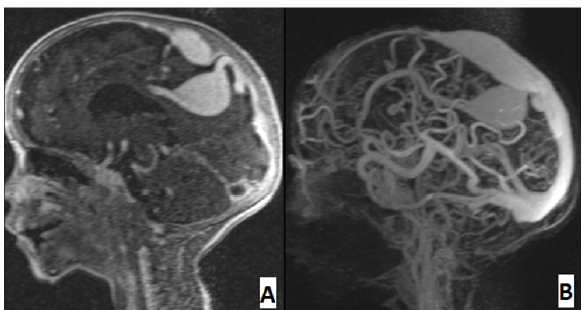

Rare Anatomical Anomaly: Aneurysmal Malformation of the Falcine Sinus in a Pediatric Patient

Abir Lemrabet, Yassine Zerhari, Hajar Zebbakh, Nazik Allali, Latifa Chat and Siham El Haddad. 12(6): 30-34.